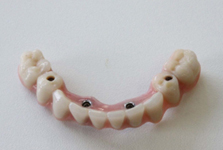

Pevné můstky – lepené nebo šroubované

Třmeny

Kulové attachmenty

Sub-Tec Locator®

S pomocí zubních implantátů můžeme díky různým kotevním systémům (třmeny, kulové hlavy, Locatory) zajistit stabilitu a držení protézy nebo při použití většího počtu implantátů zhotovit pevné náhrady – můstky nalepené nebo našroubované na pevno na implantáty.

Protetické řešení může být pomocí můstku, který je kotvený na implantátech nebo pomocí jednotlivých korunek na implantátech.

V zásadě je možné do těchto můstků zařadit i přirozené zuby, zejména pokud je potřeba tyto zuby ošetřit proteticky – korunkami. Korunky nebo můstky mohou být na implantáty nacementovány nebo přišroubovány.